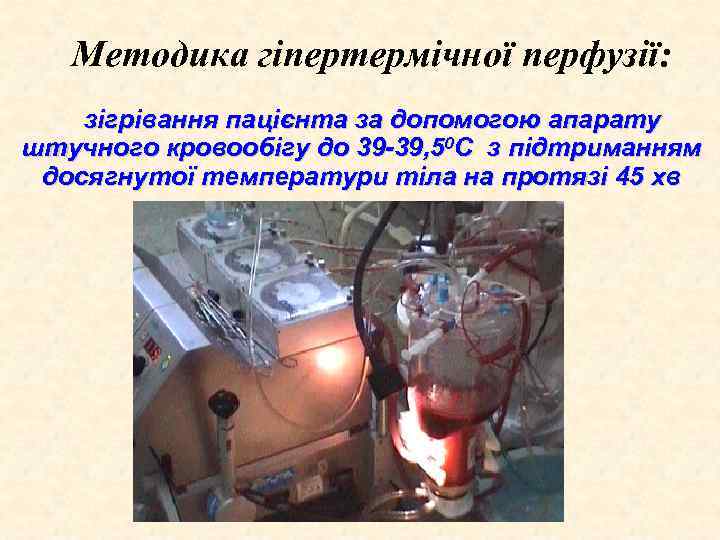

Методика гіпертермічної перфузії: зігрівання пацієнта за допомогою апарату штучного кровообігу до 39 -39, 50 С з підтриманням досягнутої температури тіла на протязі 45 хв